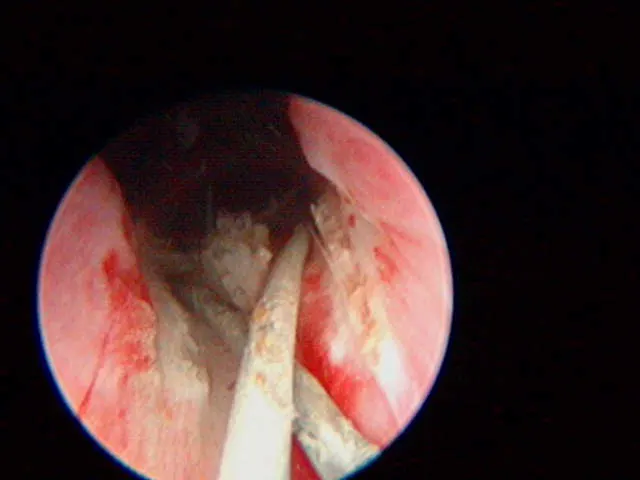

A

The plastic stent has been placed in the EU and the laser (green tip) is ablating the tissue over the stent.